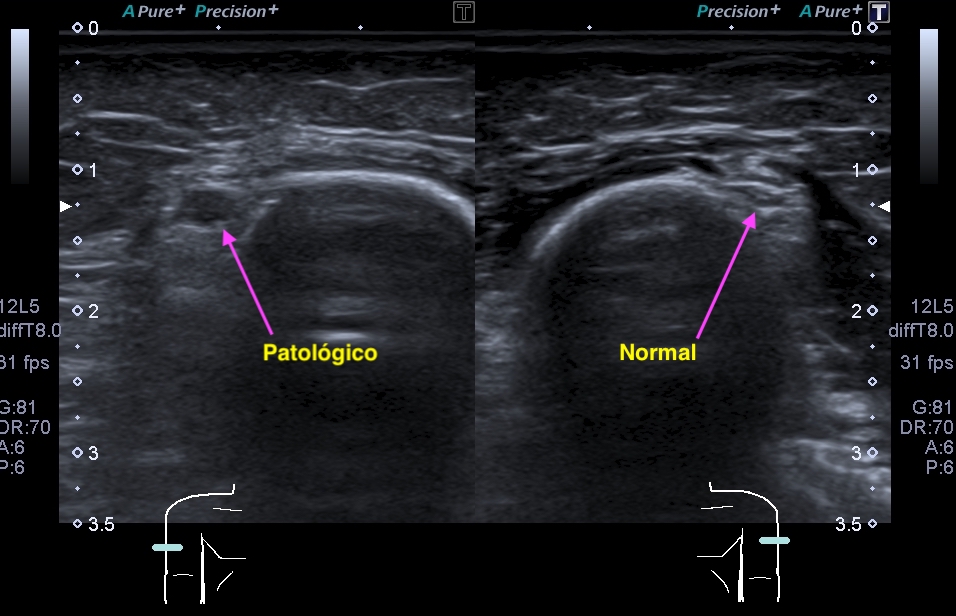

La radiografía revela aumento de las partes y se refrenda en la ecografía como puedes ver en la imagen aunque aún no hay afectación en el hueso en el caso que te presento hoy.

Ecografícamente y debido a su levedad, en el caso de hoy solo observamos cambios en las partes blandas de la cara lateral de la cabeza del quinto metatarsiano, este tejido se muestra heterogéneo, la cortical del hueso ligeramente prominente sin afectación de la misma.